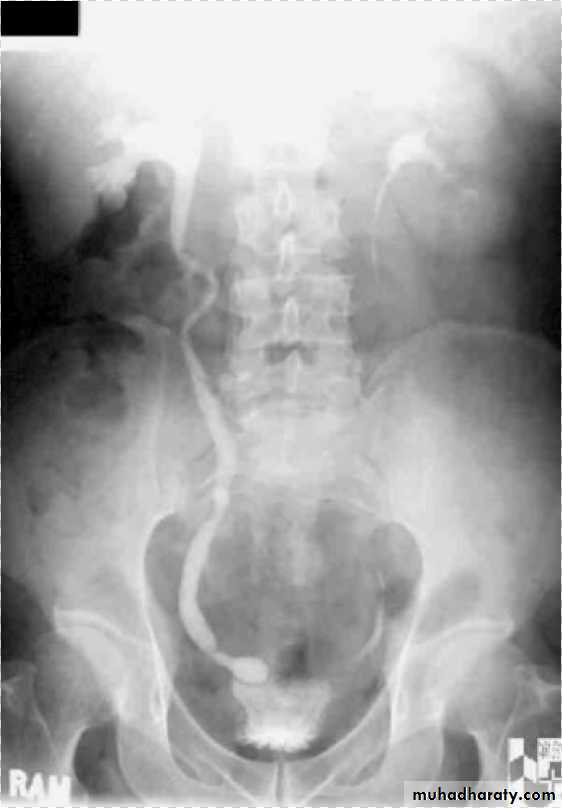

Ureterocele :

Congenital cystic dilatation of lower end of ureter ( intra-mural part) due to pin-hole meatus . May be simple or ectopic .

simple : the orifice is in proper position of bladder ,

Ectopic >> in bladder neck , urethra , uterus & vagina .

IVU :

- There is rounded or elliptical dilatation of lower end of ureter with thin lineal filling defect around it , resembling (cobra head appearance),

- Proximal dilatation of rest of ureter .

- In advanced cases hydronephrosis .

- In obstructed ureterocele , filling defect in the bladder